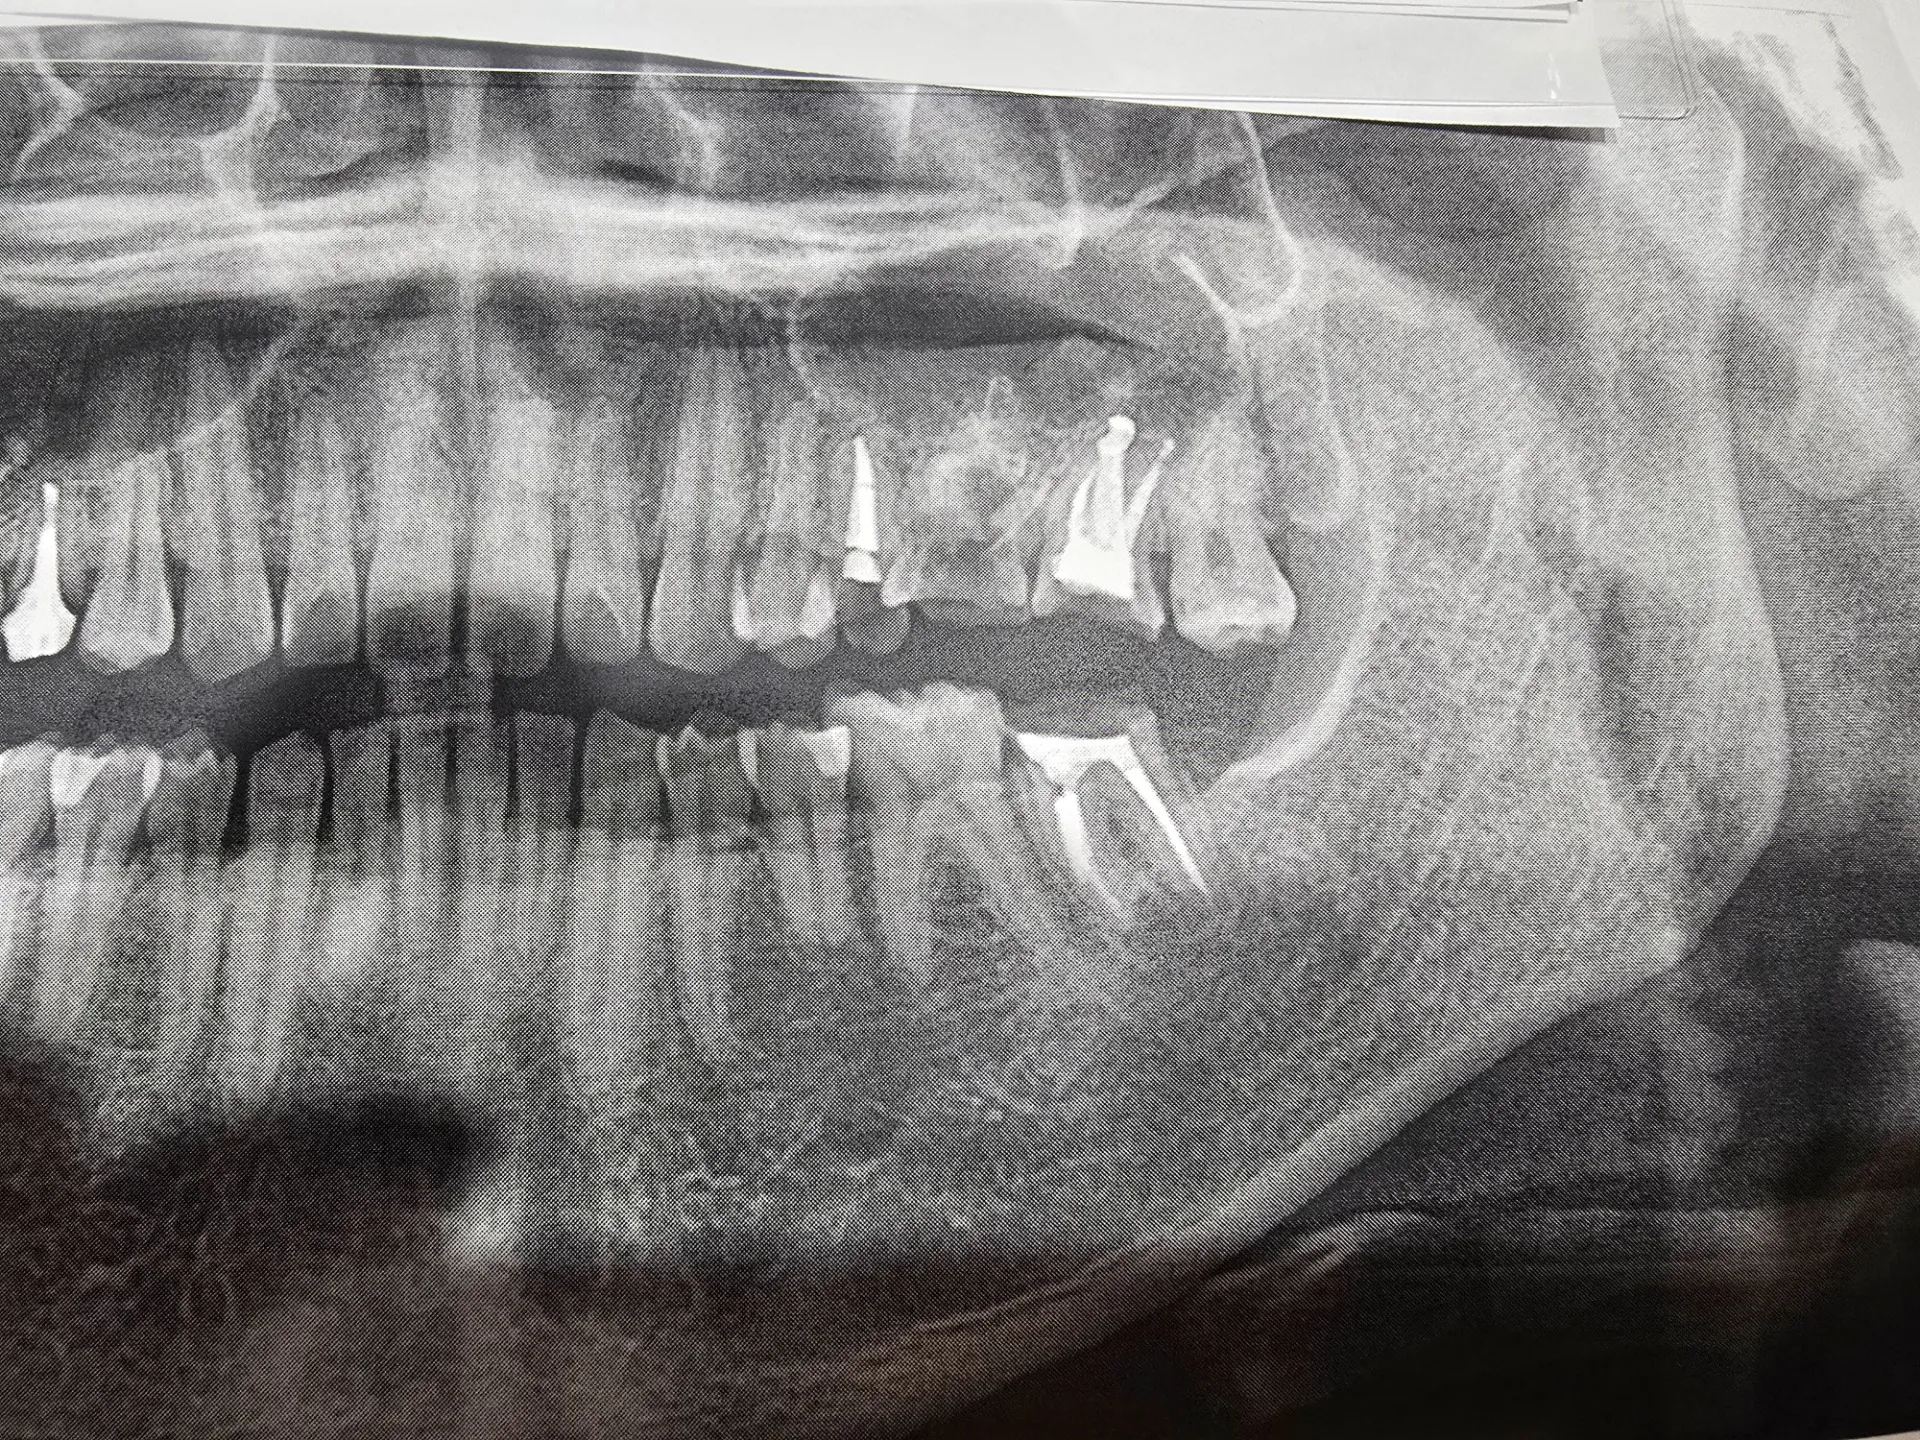

下の歯が上に上がってきている。

それ、実はよくある現象です。結論からいうと「歯が伸びた」のではなく、噛み合う相手がいなくなって歯が動いてきた状態です。

→ 歯がそのスペースに向かって動く(挺出)

👉 挺出(ていしゅつ)